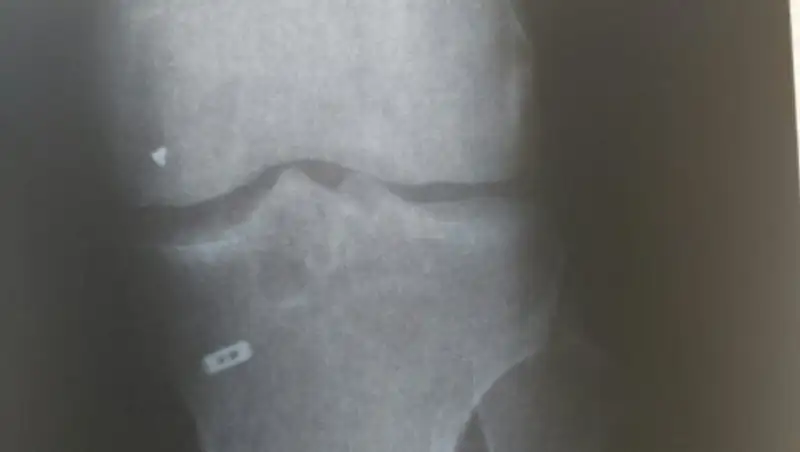

"Согласно заключению врача высшей категории, к.м.н., доцента Грушина Ю.В., состояние после пластики передней крестообразной связки с признаками ее несостоятельности. Признаки воспалительного процесса в эпифизе большеберцовой кости. Инородное тело в проекции медиального ретинакулума. Синовит. Другими словами, после операции в коленном суставе остался металлический предмет, что влечет за собой воспаление сустава. После обращения в клинику НИИТО с вопросом, как инородное тело осталось в колене, клиника НИИТО поясняет что, возможно, это кусок от инструмента, которым была произведена операция. Клиника предложила извлечь данный предмет, оплатив лишь перелет", - рассказал мужчина.